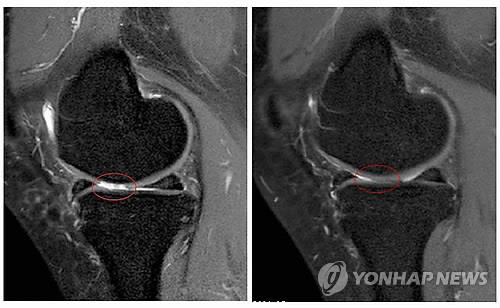

(서울=연합뉴스) 한성간 기자 = 자신의 지방조직에서 채취한 자가지방세포 이식이 퇴행성 관절염 치료에 효과가 있다는 연구결과가 나왔다.

세포치료·면역요법 국제컨소시엄(International Consortium for Cell Therapy and Immunotherapy)의 야로슬라프 미할레크 박사는 자가지방세포 이식이 퇴행성 관절염의 증상을 완화하고 손상된 관절을 일부 회복시키는 효과가 있다는 임상시험 결과를 발표했다고 의학뉴스 포털 메디컬익스프레스(MedicalXpress)가 16일 보도했다.

퇴행성 관절염 남녀환자 1천114명(평균연령 62세)을 대상으로 진행된 임상시험에서 각자에게서 떼어낸 지방조직 샘플에서 기질혈관분획(SVF)세포를 채취, 손상된 관절에 이식하고 12~54개월 동안 지켜본 결과 이 같은 효과가 나타났다고 마할레크 박사는 밝혔다.